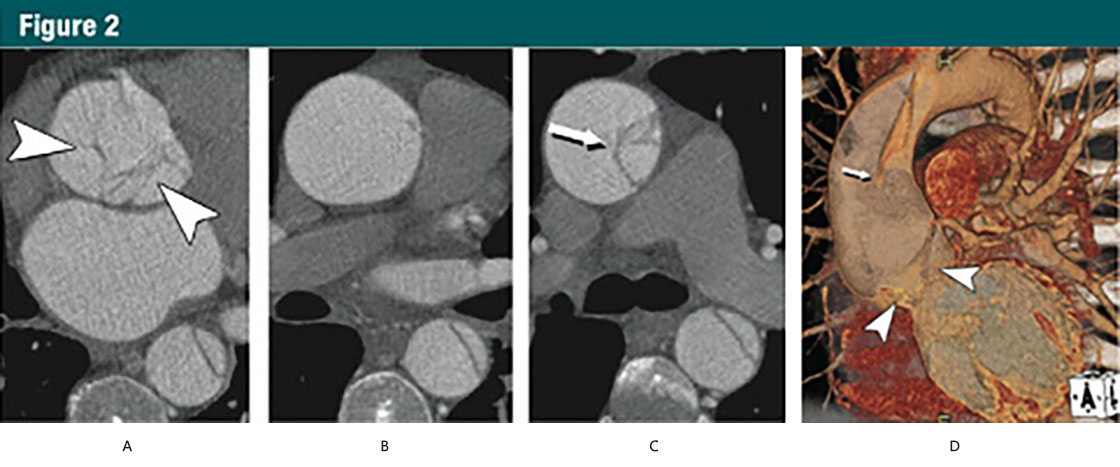

圖2 45歲,男,A型急性主動脈夾層

(A-C)CT橫斷位圖像:

(A)主動脈根部水平不規則線樣陰影(箭頭)

(B)升主動脈中(zhōng)段沒有夾層皮瓣

(C)升主動脈遠端可見夾在真、假腔之間的夾層皮瓣(細箭)

(D)VR重建展示夾層,近端夾層撕裂皮瓣下(xià)垂向下(xià)通過主動脈瓣膜(箭頭)。細箭所指遠端升主動脈的夾層皮瓣。在無ECG門控的時候,這些細微的發現并不可見。(轉載、許可、引用30)

由于有着共同的病理改變,代表主動脈夾層及其變異的第一(yī)組病變都是動脈壁中(zhōng)層病變。典型夾層的征象是主動脈壁内形成一(yī)個通道或者假腔,後者通過撕裂的内膜與真腔分(fēn)離(lí)(圖2)。

Group 1 lesions representing aortic dissection and its variants share a diseased aorticmedia as their common pathologic lesion. Classic dissection is characterized by the development of a flow channel or false lumen within the aortic wall, which is separated from the true lumen by a dissection membrane (Fig2).